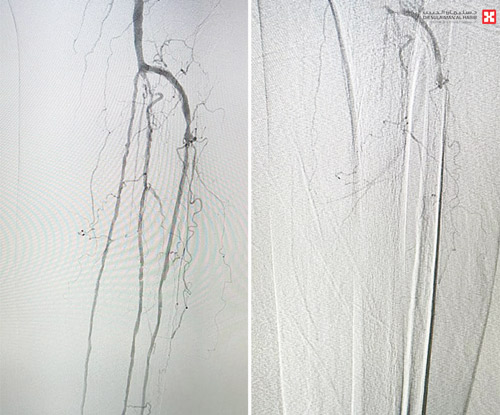

وقال البشري إنه تم تقييم حالة الشرايين لدى المريضة وبناءً على نتائج التقييم تقرر إجراء قسطرة توسيعية دقيقة لشرايين الساق والقدم. وقد استمرت العملية ساعة ونصف باستخدام أحدث الأجهزة والتقنيات التداخلية لإعادة التروية الدموية إلى القدم، مما ساهم بشكل مباشر في استعادة تدفق الدم بشكل فعّال وتجنّب بتر القدم، وقد غادرت المريضة المستشفى في اليوم التالي من العملية وهي بحالة مستقرة.